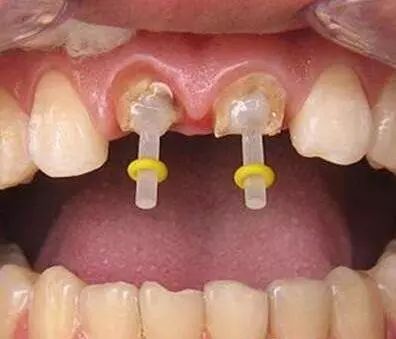

一些人在进行根管治疗后,会进行牙齿打桩。牙齿打桩是指在患者牙齿缺损较大,或因为外伤等原因只剩下牙根时,因剩下的牙齿过短或力量过于薄弱,不能用修复体直接修复,需要给牙根里打桩,加固并延长折断的牙齿,以使假牙能获得足够的力量固定。下面口腔专家给大家具体介绍一下牙齿打桩的相关知识。

牙齿打桩是指插入根管内的部分,利用摩擦力和粘固力、粘接力获得固位,进而为最终修复体提供固位。

牙齿桩的长度应该大约有牙槽骨支持的根长的1/2,即骨内桩长度大于骨内根长度的1/2,这样桩的末端不至于离牙槽脊太近,极大程度的减少根折。

一般来说,在桩材料强度足够的条件下,桩的直径在1/4到1/3根径范围内都对牙根的抗折性无明显影响。